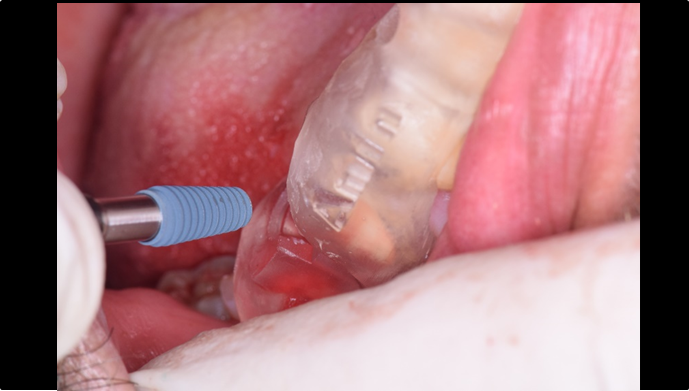

“ONE-DAY implant, one-day smile

”

Clinical case: : R2GATE guided surgery & immediate implant placement

- Courtesy of Dr. Kwang Bum Park, Korea -